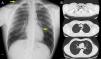

Complete blood count with serum proteins were normal. Serum biochemistry showed vitamin B12 levels of 172.1pg/ml. Chest radiograph on admission (Fig. 1A) showed an area of left paracardiac hyperlucency, consistent with pneumomediastinum. A chest computed tomography (CT) was performed to confirm the diagnosis and to complete the study.

(A) Chest X-ray, showing (arrows) signs of subcutaneous emphysema the right laterocervical region and an area of left paracardiac hyperlucency, suggestive of pneumomediastinum. (B) Chest CT (parenchymal window) showing extensive pneumomediastinum in several regions, dissecting the mediastinal structures.

On computed tomography (Fig. 1B), the most significant findings were a large pneumomediastinum that dissected the mediastinal structures and extended along the left oblique fissure. It was also accompanied by subcutaneous emphysema in both laterocervical regions, the supraclavicular fossa (predominantly in the left side), and both axillary regions. Neither pneumothorax nor rib fractures were observed.